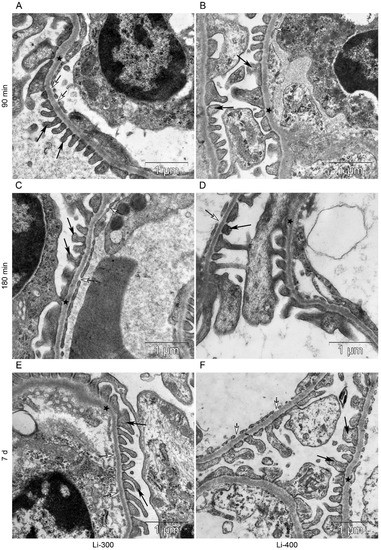

All components of the mice kidney filtration barrier in the control group had a typical ultrastructural organization (Figure 6). Fenestrae of endotheliocytes of glomerular capillaries were well expressed. The heterogeneity of the ultrastructural organization of podocytes was noted. Podocyte foot processes often varied in thickness. The glomerular membrane and basement membrane of proximal tubular epitheliocytes had equable density and thickness. Lithium administration at a single dose of 300 mg/kg and 400 mg/kg did not lead to a significant change in the structure of the kidney filtration barrier (Table 4; Figure 7 and Figure 8). There were no statistically significant differences between the lithium-treated and control groups.

Figure 8.

The structure of basement membrane (asterisks) of proximal tubular epitheliocytes at (A,B) 90 min, (C,D) 180 min and (E,F) 7 d after peroral lithium carbonate administration at single doses of 300 (Li-300) and 400 (Li-400) mg/kg.